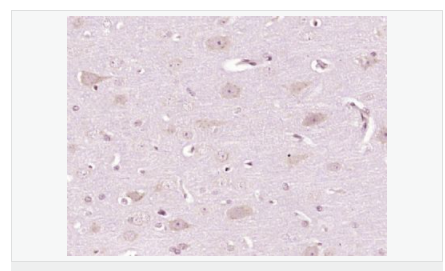

| 產(chǎn)品應(yīng)用 | WB=1:500-2000 IHC-P=1:100-500 IHC-F=1:100-500 ICC=1:100-500 IF=1:100-500 (石蠟切片需做抗原修復(fù)) not yet tested in other applications. optimal dilutions/concentrations should be determined by the end user. |